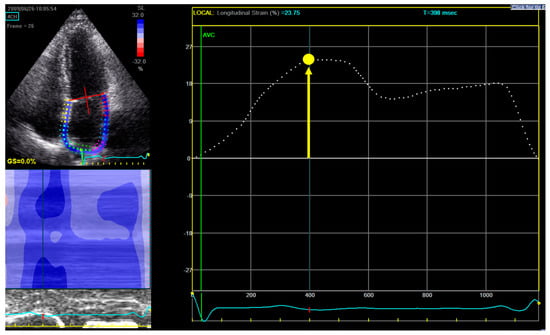

For measuring LA longitudinal strain, a dedicated non-foreshortened apical 4-chamber view was used, and the endocardial border tracing was started at the septal part of the mitral annulus, extrapolated across the pulmonary veins and LA appendage and ended at the opposite mitral annulus side (Figure 1) [16].

Figure 1. Measurement of left atrial reservoir strain (εR). Upper-left panel shows the selection of the region of interest: in a dedicated non-foreshortened apical 4 chamber view, the tracing begins at the level of the endocardial border of the mitral annulus; it is then continued along the endocardial surface of the left atrium extrapolating across the orifices of the pulmonary veins and left atrial appendage, ending at the opposite side of the mitral annulus. Right panel displays the left atrium longitudinal strain curve: the zero-reference point is at end-diastole and εR is calculated as the difference between the strain value at the mitral valve opening and ventricular end-diastole (positive value). In this example in a patient from our study, εR is 23.75%.

From the LA strain curve, ƐR was measured as the positive peak systolic value within LV end-diastole (mitral valve closure) and mitral valve opening [16]. The zero-reference point was chosen at LV end-diastole (onset of QRS). ƐR was selected as the parameter to assess LA function, since it was shown in previous literature to have the best reproducibility and feasibility (also in atrial fibrillation patients) and the strongest prognostic value [17,18,19].